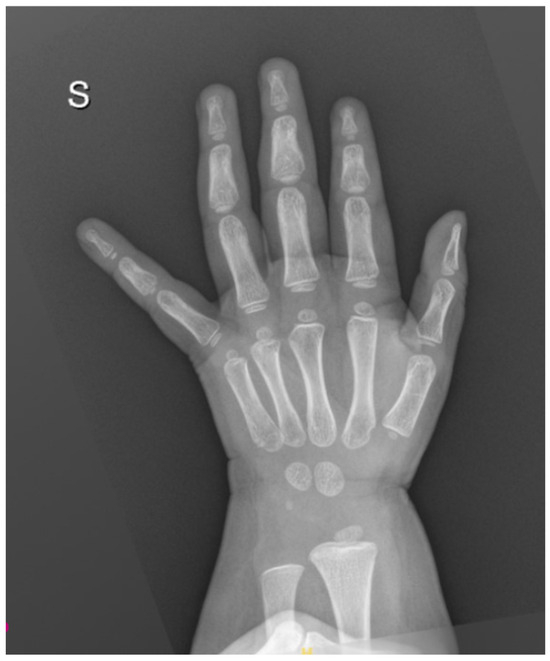

Background and Clinical Significance: Scurvy, caused by chronic vitamin C deficiency, is re-emerging in Western countries, particularly among pediatric patients with highly selective diets. While its musculoskeletal and mucocutaneous manifestations are well-known, its association with pulmonary arterial hypertension (PAH) is rare and poorly understood. Ascorbic acid and iron are essential cofactors for prolyl hydroxylases (PHD), which regulate Hypoxia-Inducible Factors. Their combined deficiency may trigger a “pseudohypoxic” state, leading to pulmonary vascular remodeling and vasoconstriction. Case Presentation: A 30-month-old female presented with a one-month history of limping, lower limb pain, and gingival hypertrophy. Dietary history revealed an almost exclusive cow’s milk-based intake. Physical examination showed diffuse petechiae, pallor, and right knee edema. Laboratory findings confirmed scurvy (undetectable vitamin C), severe iron-deficiency anemia (Hb: 72 g/L; ferritin: 22 mcg/L; RDW: 30%), folate deficiency, and hyperhomocysteinemia. Notably, elevated copper and vitamin B12 levels suggested a state of metabolic dysregulation. Echocardiography revealed moderate PAH phenotype (estimated sPAP: 47–50 mmHg) and a hyperdynamic contractility. A “perfect storm” mechanism was hypothesized, involving iron–ascorbate-dependent PHD impairment, high-output state, and oxidative-stress-induced hepcidin dysregulation (suggested by elevated copper). Following intravenous vitamin C and multivitamin supplementation, pulmonary pressures normalized within one week. Conclusions: PAH phenotype in scurvy represents a reversible metabolic disruption of pulmonary vascular tone rather than a structural disease. This case underscores the synergistic role of vitamin C, iron, and folate in vascular homeostasis. Clinicians should maintain high suspicion for scurvy in children with selective diets and unexplained PAH, as nutritional restoration is curative. Full article